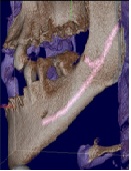

Trifid Mandibular Canal and Lingual Accessory Mental Foramen: A Case of Two Rare Anatomical Variations

Seda Ozgedik, Umit Karacayli, Savaş Ozarslanturk, Hakan Avsever*, Kaan Orhan